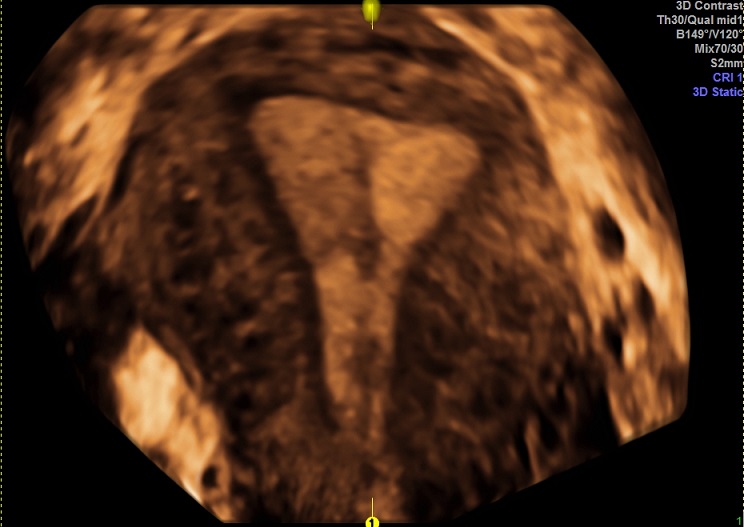

女性,28岁,继发性不孕2年。

2015-1-28 月经第24天检查

内膜厚0.6cm

容积:3.4ml